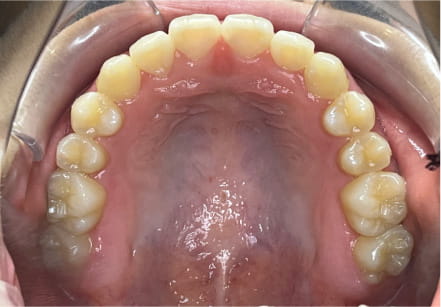

叢生の症例

25歳

男性

左上の奥歯と全体の噛み合わせを矯正したい

左上5抜歯の場合は要相談、右上8抜歯OK紹介する、拡大・遠心移動・IPR予定

全額アライナー矯正

クリアライナー使用

痛み・歯根吸収・歯肉退縮・虫歯・後戻り

780,000円、2年2ヶ月